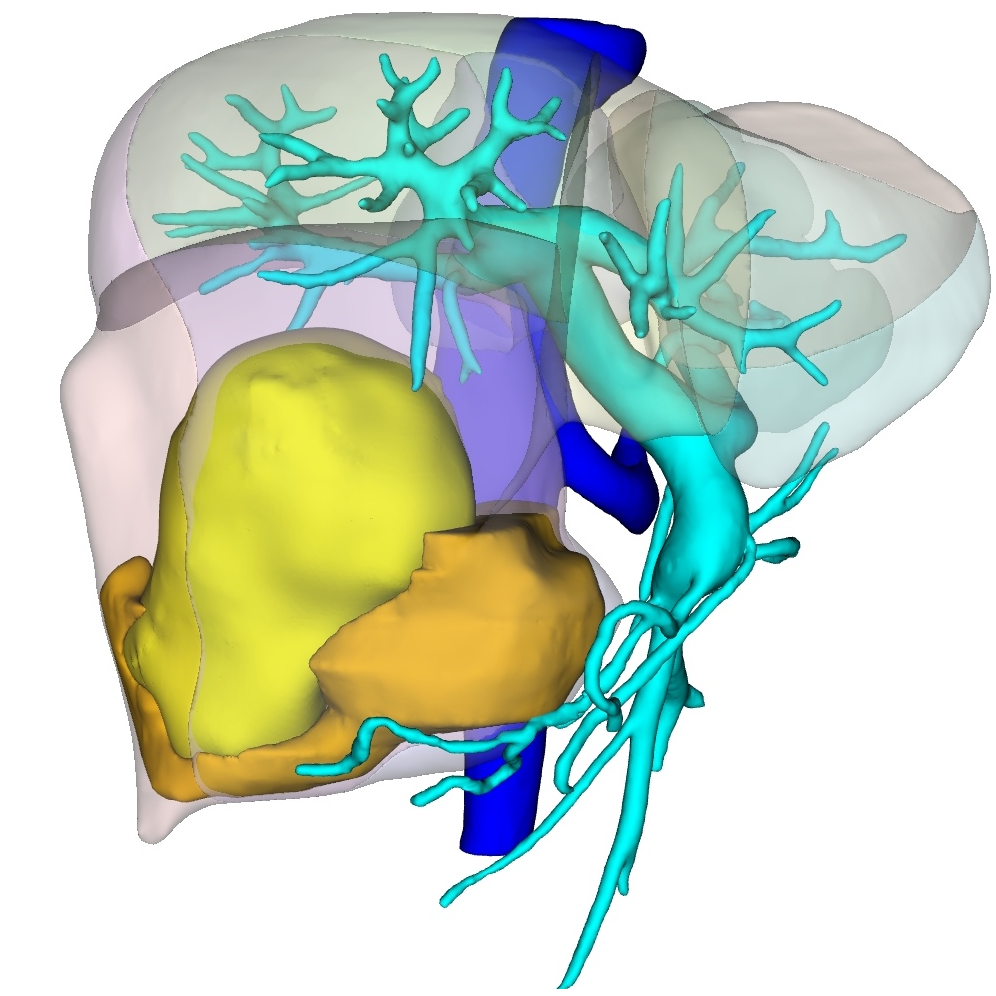

肝癌专病中心MDT于2025年9月正式启动,运行半年来严格落实常态化诊疗机制,成效显著。中心坚持每周2次规范化多学科讨论,打破科室诊疗壁垒,汇聚肝胆、消化、肿瘤、影像、病理、肝病等多学科精锐力量,聚焦各类肝癌的精准诊疗需求。截至目前,已为40余例肝恶性肿瘤患者开展MDT联合诊疗,量身定制手术切除、介入治疗、靶免联合等个性化诊疗方案;2025年肝胆诊疗中心完成100余例肝脏手术,涵盖高难度精准肝切除、腹腔镜及机器人肝切除、5G远程机器人手术,以硬核技术提升诊疗效果,赢得患者及家属广泛认可。